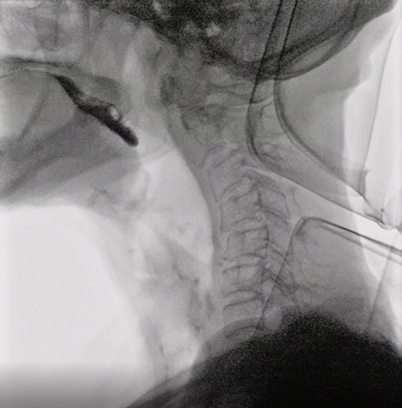

②入院・VF検査(飲み込みのレントゲン検査)

入院初日にVF検査を実施し、嚥下状態を詳しく確認します。